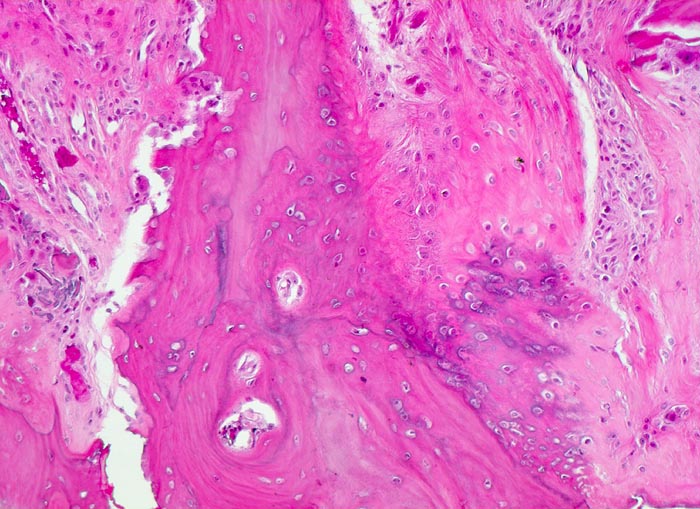

Makroskopisch ist die Nekrose im Anfangsstadium durch eine intensiv gelbe Verfärbung mit hämorrhagischem Randsaum charakterisiert. Häufig kommt es zur flächenhaften Ablösung des ansonsten intakten Gelenkknorpels (DD Arthrose!) zwischen subchondraler Knochenlamelle und angrenzender Spongiosa. In den Spätstadien sind die Nekrosezonen grau-gelb gefärbt und von körniger Konsistenz. Ein Teil der nekrotischen Spongiosabälkchen dient als Leitschiene für die Neubildung von Osteoid und mineralisierten Trabekeln, die an der Aussenseite angelagert werden. In der Nekrosezone kommt es zur Sequestrierung von Knochenbälkchen durch Frakturen. Die Markräume werden bindegewebig organisiert. In der Peripherie besteht initial ein hyperämischer Randsaum und im Verlauf kommt es zur Ausbildung einer metaplastischen Knorpel- und Knochenneubildung mit Randsklerose. Das Endstadium der Abräumreaktion untergegangener Knochenabschnitte stellt eine meist subchondral lokalisierte pseudozystische Umwandlung dar. Schliesslich kollabiert der Femurkopf und der Verlust der Gelenkkongruenz führt zu einer fortschreitenden sekundären Coxarthrose (> 3192)

• Flächenhafte Ablösung des gut erhaltenen Gelenkknorpels zwischen subchondraler Knochenlamelle und angrenzender nekrotischer Spongiosa.

• In der Nekrosezone osteoklastäre Resorption von avitalen sequestrierten Spongiosabälkchen.

• Ortsständiger Lamellenknochen wird als Leitschiene zur Fasernknochenneubildung benutzt.

• Pseudozystische Hohlräume in den nekrotischen Markräumen.

• Fibrosiertes Mark mit einzelnen thrombosierten Arterien.